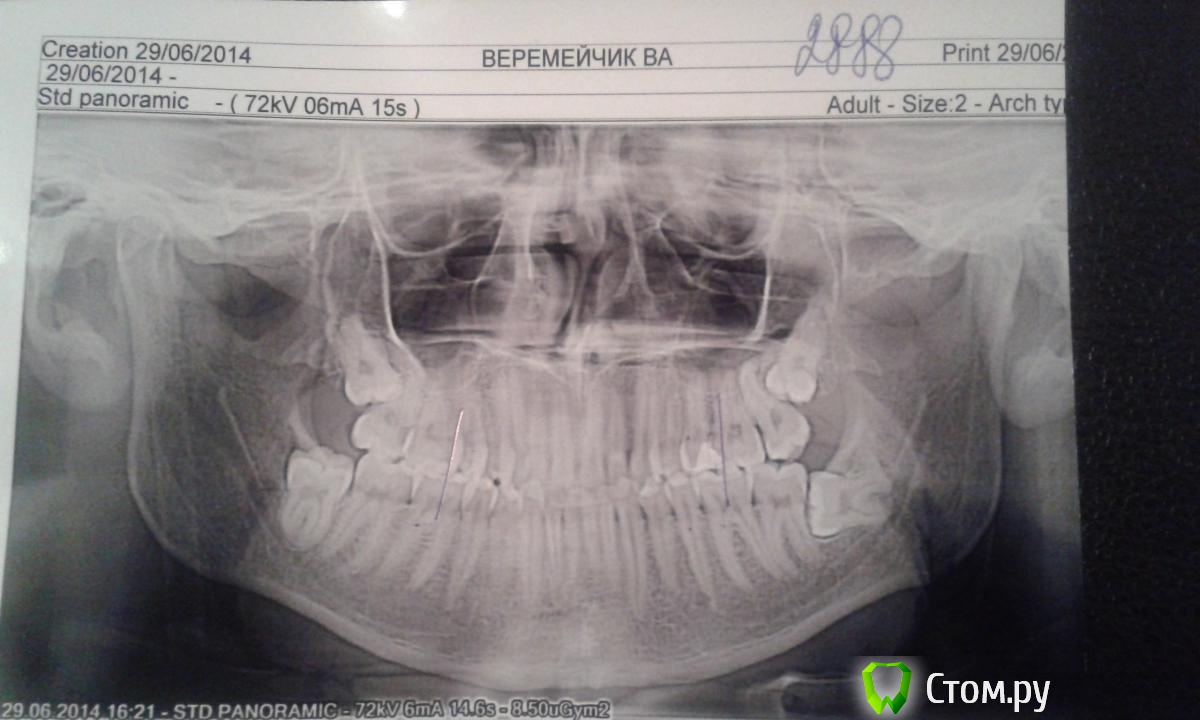

DokDent Опубликовано 1 июля, 2014 Поделиться Опубликовано 1 июля, 2014 Так все таки правильно снимок расположен? Думаю да. Вот 2 снимка-обратите внимание на буквы и цифры Ссылка на комментарий

Bier Опубликовано 1 июля, 2014 Поделиться Опубликовано 1 июля, 2014 Олег, не пойму: а надписи почему тогда читаются правильно? Если снимок наоборот, то и надписи вроде должны быть наоборот?Вы правы, я ошибся. Но перелом там, где я написал 38 зуб надо будет потом удалить, месяца через 3-4, а то при удалении челюсть еще раз сломают ) 1 1 Ссылка на комментарий

DokDent Опубликовано 1 июля, 2014 Поделиться Опубликовано 1 июля, 2014 Вы правы, я ошибся. Но перелом там, где я написал Скорей всего Василий ошибся со стороной перелома Ссылка на комментарий

kriokov Опубликовано 2 июля, 2014 Поделиться Опубликовано 2 июля, 2014 (изменено) топикстартеруВас боли, отек, боли при жевании с какой стороны беспокоят, справа?Иммобилизация челюсти в любом случае для Вас показана.Ну и снимки новые не повредят, как уже сказали Ну покажите мне линию перелома коллеги . . .то же не увидел. Сравнивал кортикальную канала, он вроде четко виден, нигде не прерывается, и не смещается. Изменено 2 июля, 2014 пользователем kriokov 1 Ссылка на комментарий

ПалСаныч Опубликовано 2 июля, 2014 Поделиться Опубликовано 2 июля, 2014 Я считаю что линия перелома в области 48 есть, она крива и прослеживается сверзу донизу ( видно по кортикалке), но я и с подозрениями Олега Юрьевича согласен, я б на область 38 обратил внимание тоже. В плане тактики ничего не изменится, а если станет вопрос о тяжести травмы и страховых выплахтах, то за двусторонний перелом дают больше))) Ссылка на комментарий